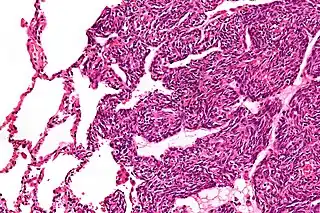

![]() Micrografía de un sarcoma sinovial monofásico. El aspecto histológico es inespecífico y se superpone con MPNST y fibrosarcoma. Tinción H&E. | ||

Dos tipos de células pueden verse microscópicamente en el sarcoma sinovial. Un tipo fibroso, conocido como huso o célula sarcomatosa, es relativamente pequeño y uniforme, y se encuentra en láminas. El otro es epitelial en apariencia. El sarcoma sinovial clásico tiene una apariencia bifásica con ambos tipos presentes. El sarcoma sinovial también puede parecer poco diferenciado o ser fibroso monofásico, que consiste solo en láminas de células fusiformes. Algunas autoridades[8] afirman que, muy raramente, puede haber una forma epitelial monofásica que causa dificultad en el diagnóstico diferencial. Dependiendo del sitio, existe una similitud con el sarcoma sinonasal bifenotípico, aunque los hallazgos genéticos son distintivos.